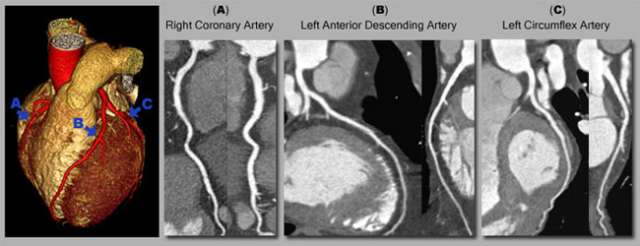

Example Case Study: coronary CT in a 67 year-old female patient provides excellent image quality with a low radiation dose. With prospective ECG triggering, the X-ray beam is turned on during the required heart phases rather than the entire cardiac cycle. This reduces the delivered radiation dose by about 70 to 90% compared to standard, retrospectively gated acquisitions. (Actual radiation dose may vary based on clinical indication and protocol)